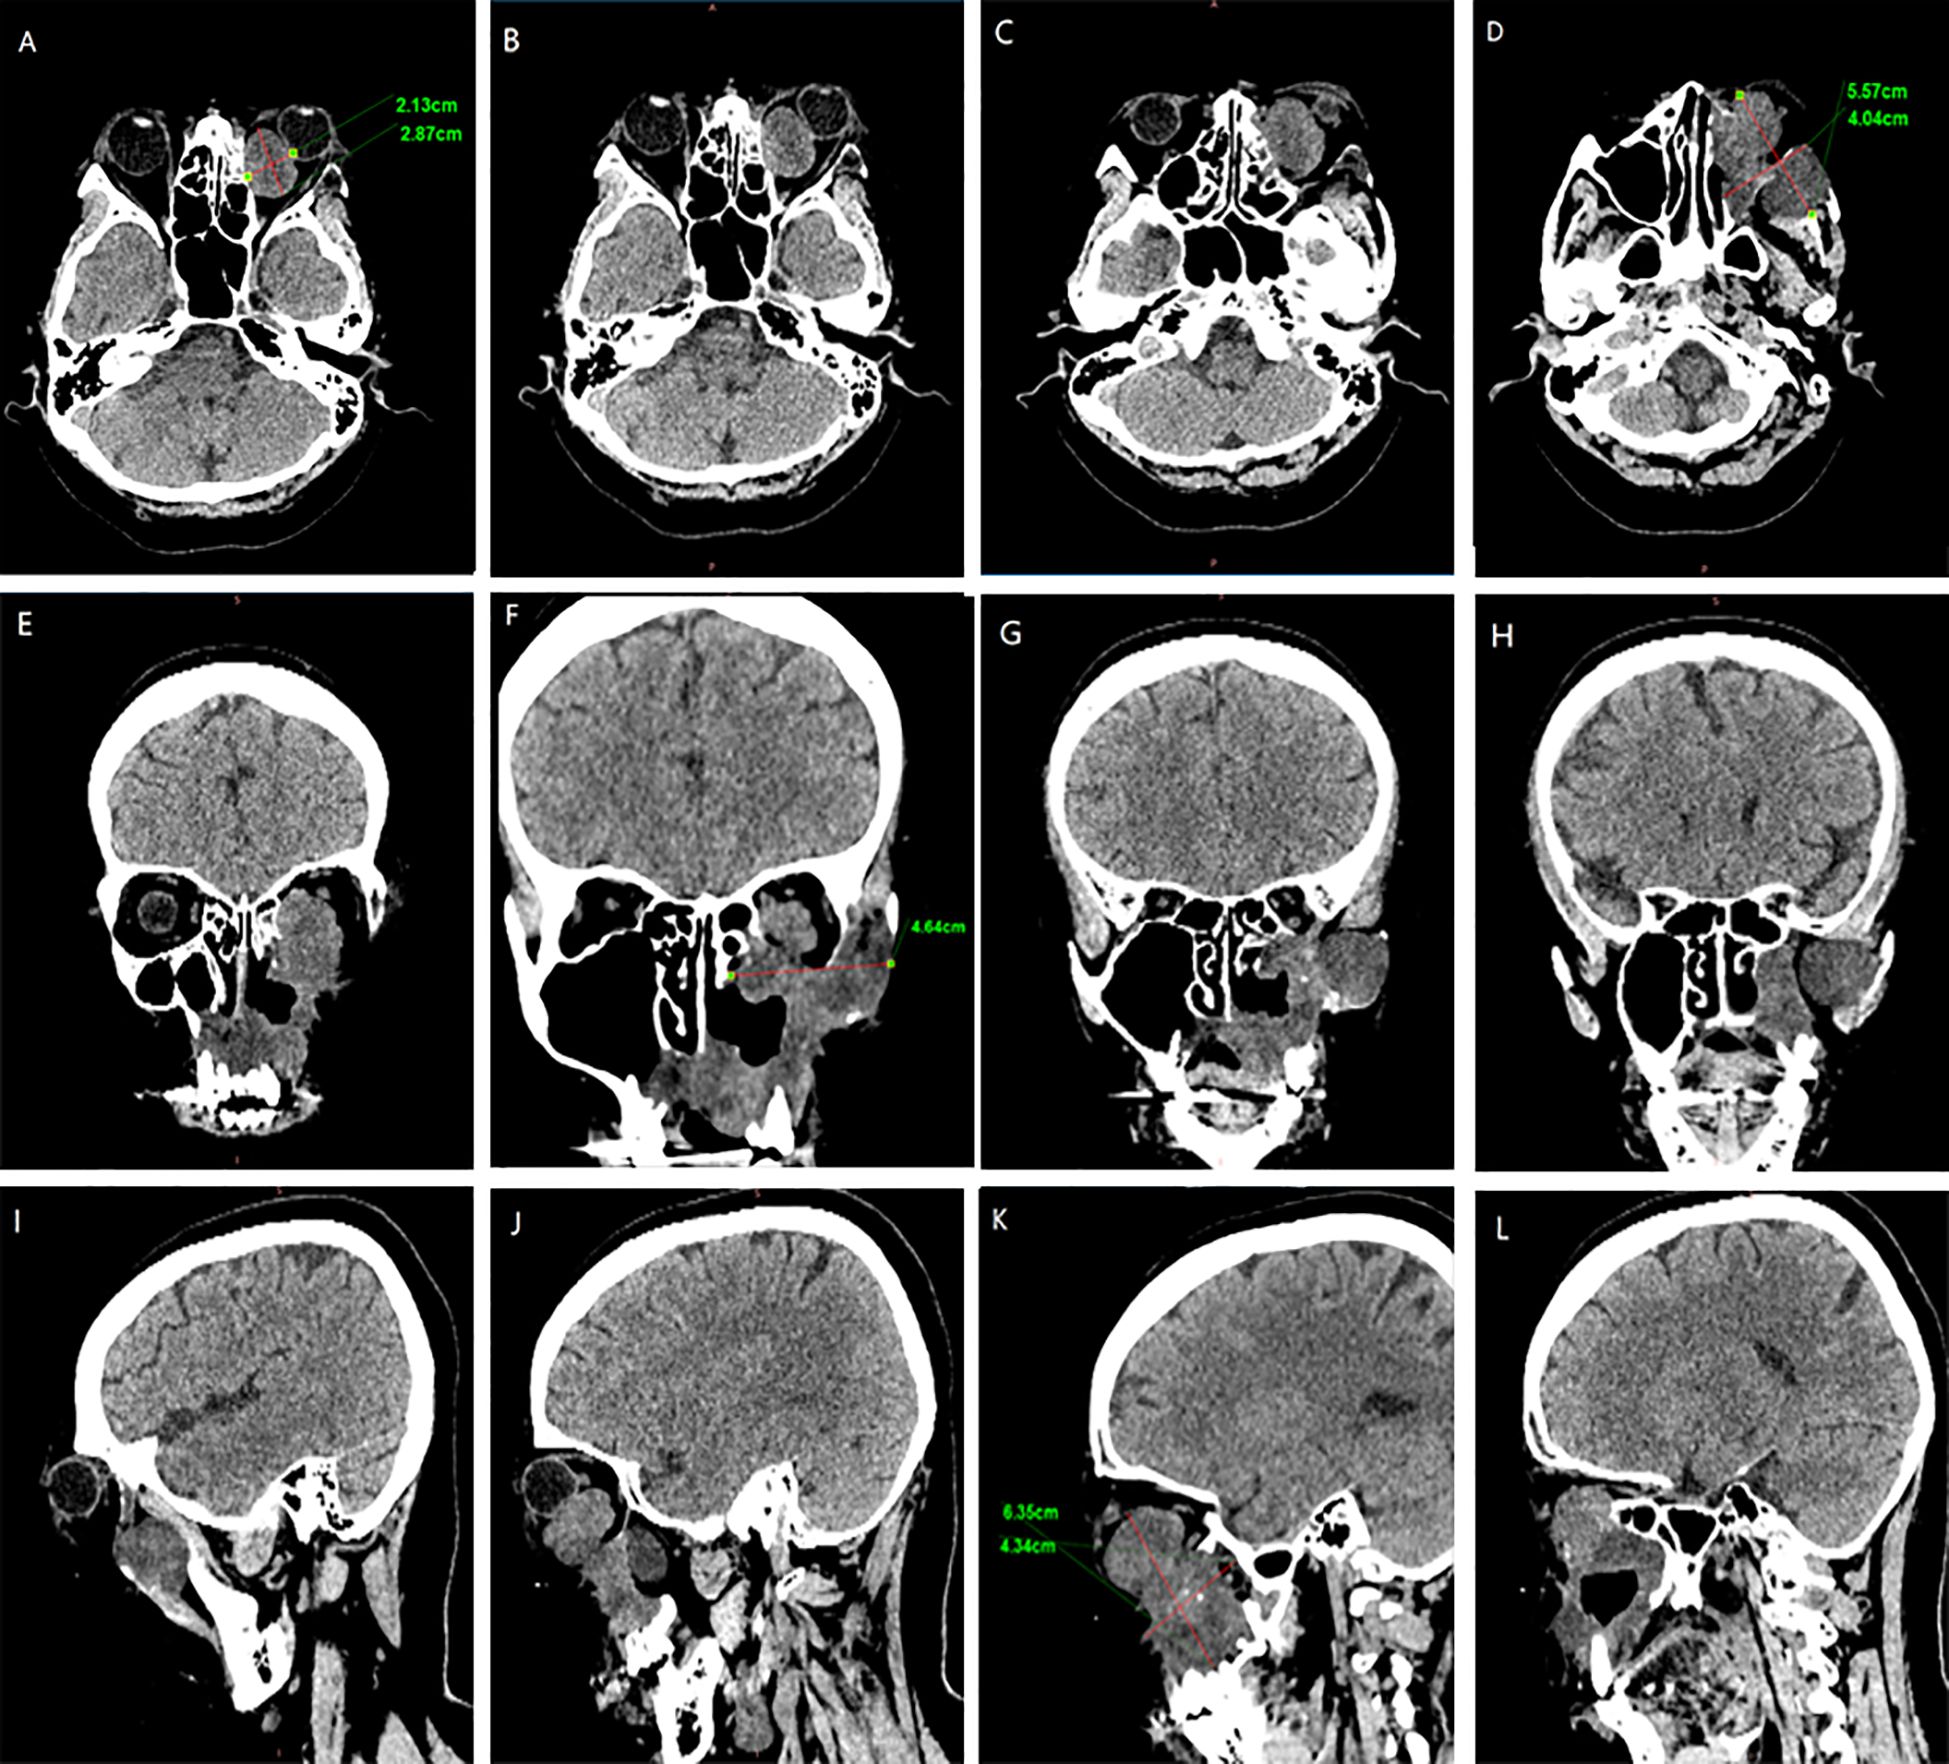

In February 2024, the patient presented with recurrent symptoms including left facial swelling, left orbital displacement, diplopia, progressive visual acuity deterioration, and ocular distension. MRI revealed local tumor recurrence, demonstrating superior growth through the superior wall of the maxillary sinus into the orbital cavity, with optic nerve compression and orbital bone destruction (Figure 1). CT findings suggest tumor recurrence. (Figure 2).

Figure 2. CT Anatomical imaging: Findings consistent with (LGMFS) tumor recurrence involving the orbit. (A–D) Axial CT image. (E–H) Coronal CT image. (I–L) Sagittal CT image.

We followed up with the patient at 1 month, 3 months, 6 months, and 1 year postoperatively. After one year of follow-up, the volume of the primary tumor significantly decreased (the tumor size was approximately 5.57×4.04×6.35 cm before treatment, and 2.32×0.96×3.15 cm after treatment) (Figure 5). The intraorbital tumor decreased in size from 2.87×2.12×3.52 cm to 1.94×0.99×2.78 cm.The compression of the optic nerve by the tumor was alleviated, and both visual field and vision showed signs of recovery. The proptosis of the eyeball was significantly improved. The swelling and deformity of the eye were markedly improved, resulting in a more natural facial appearance (Figure 6). The patient’s visual acuity improved significantly from 20/200 (LogMAR 1.0) preoperatively to 20/30 (LogMAR 0.2) at 1 year postoperatively. The patient’s quality of life was significantly enhanced. No complications such as radiation-induced cataracts, optic neuropathy, or cerebral edema were observed during the last follow-up in March 2025.